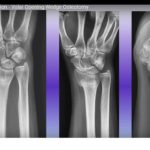

Distal radius Fracture Malunion and Corrective Osteotomy

Courtesy: Saurabh Agarwal, FRCS Tr and Orth, Princess Royal University Hospital, London, UK

• Volar Opening Wedge Osteotomy for Distal Radius Malunion